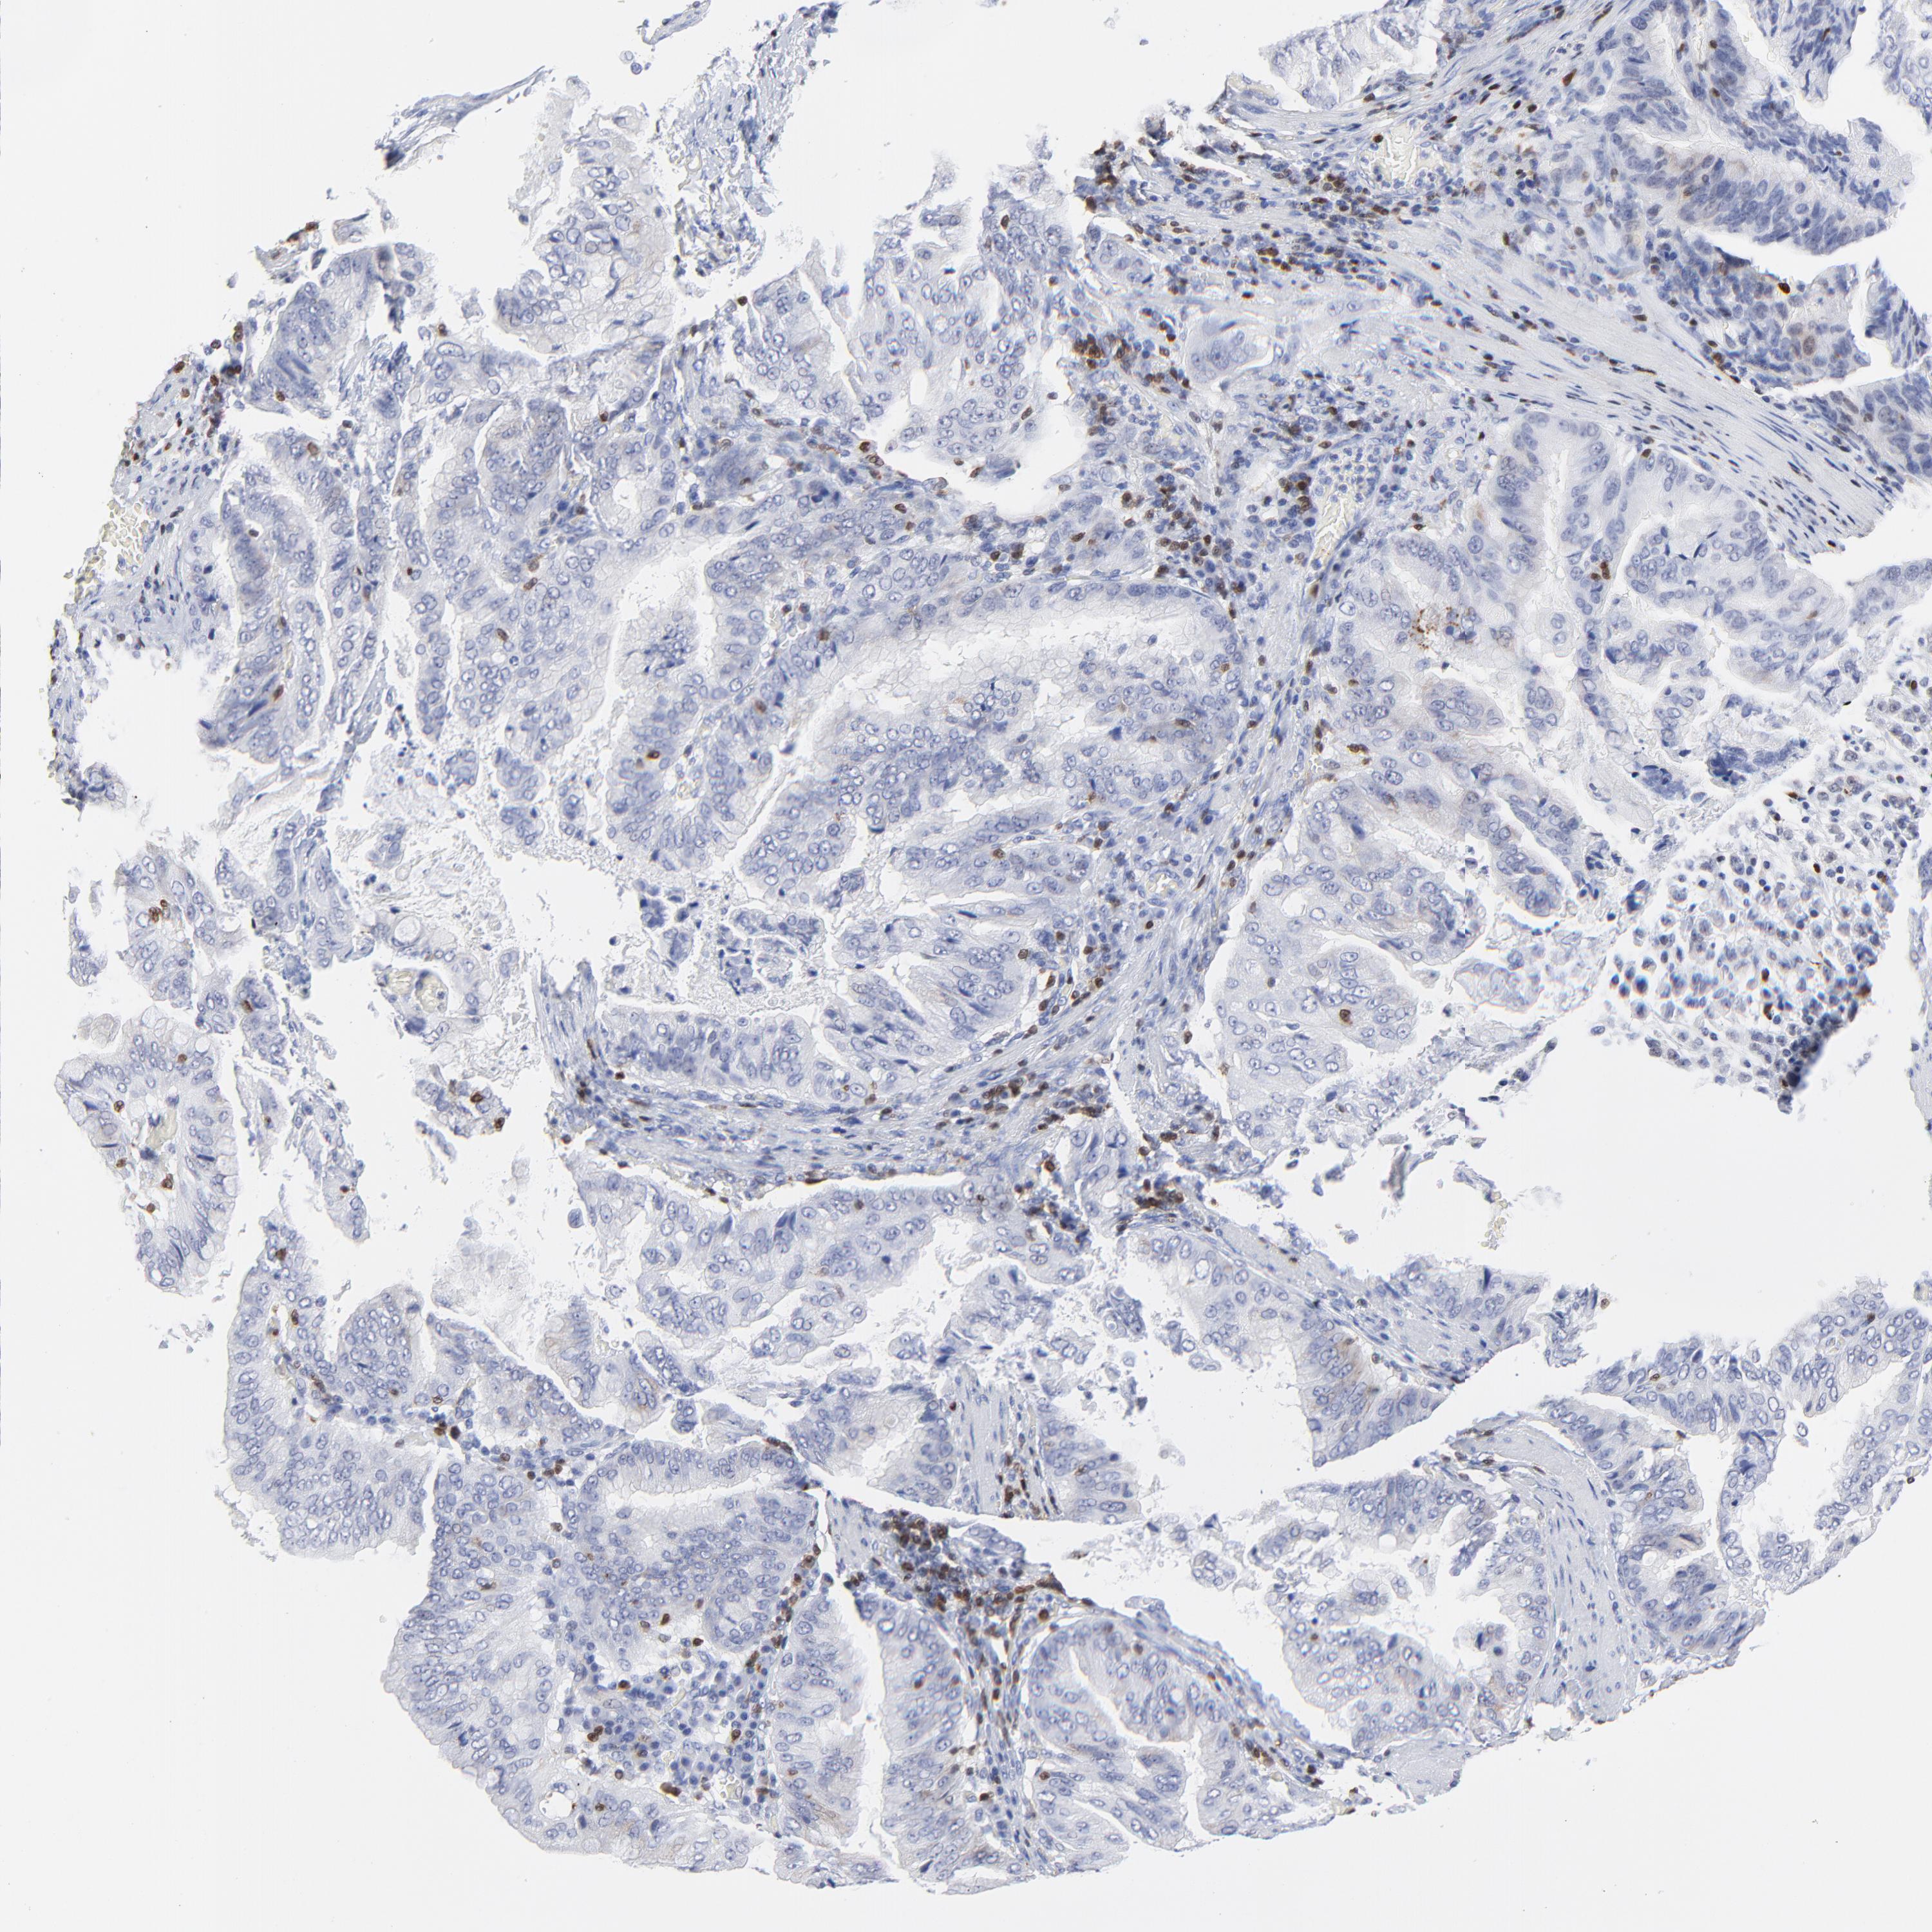

STOMACH CANCER - Protein expressioni

A mouse-over function shows sample information and annotation data. Click on an image to view it in a full screen mode. Samples can be filtered based on level of antibody staining by selecting one or several of the following categories: high, medium, low and not detected. The assay and annotation is described here.

Note that samples used for immunohistochemistry by the Human Protein Atlas do not correspond to samples in the TCGA dataset.

Antibody stainingi

Antibody staining in the annotated cell types in the current human tissue is reported as not detected, low, medium, or high, based on conventional immunohistochemistry profiling in selected tissues. This score is based on the combination of the staining intensity and fraction of stained cells.

Each image is clickable and will lead to virtual microscopy that enables deeper exploration of all samples and also displays staining intensity scores, fraction scores and subcellular localization as well as patient and tissue information for each sample.

Antibody HPA003134

Antibody CAB002625

Staining

High

Medium

Low

Not detected

Intensity

Strong

Moderate

Weak

Negative

Quantity

>75%

75%-25%

<25%

None

Location

Nuclear

Cytoplasmic/membranous

Cytoplasmic/membranous,nuclear

Adenocarcinoma, NOS